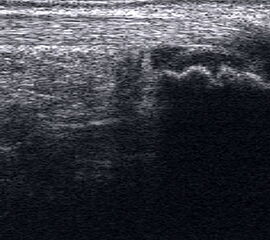

Lymphödem am oberen Sprunggelenk

Echogene Verdickung im Subkutangewebe bei Lymphödem

Abbildung 8

Lagerung: Rückenlage.

Schnittebene: Ventraler LS über dem OSG.

Referenzstrukturen: Distale Tibia und Talusrolle, darüber Gelenkkapsel. Befunde: Echogene Verdickung subkutan (Abb. 8), hier peronäal oberhalb des OSG. Bei Varicosis sind in der Subkutis erweiterte Venenkomplexe mit echoarmem Lumen und positivem Doppler-Signal zu sehen.